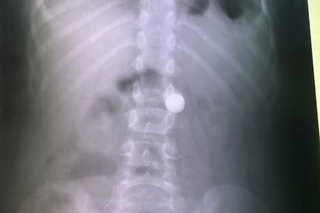

«Это время интенсивной «охоты» за случайно проглоченными монетами, деталями конструктора и косточками. Но январь 2026-го приятно удивил медиков. За все каникулы поступил лишь один юный «исследователь»: восьмилетний мальчик проглотил увесистый металлический шарик диаметром в сантиметр.

Других находок в желудках балаковцев в эти праздники не обнаружилось — это настоящий рекорд за последние годы!» — рассказала заведующая эндоскопическим отделением Элла Бобрышева.